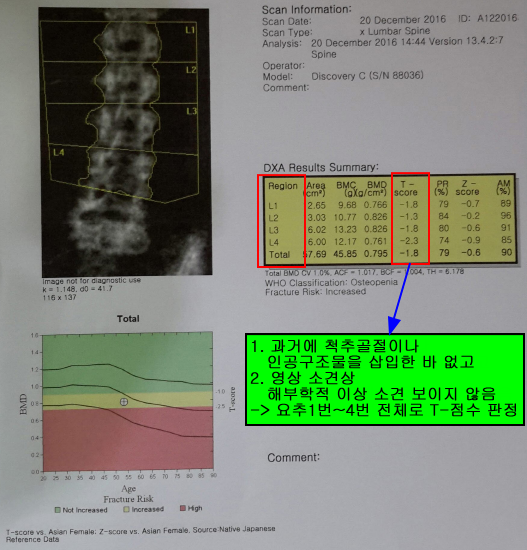

골밀도가 조금씩 감소하면서 뼈는 약해지고, 작은 자극에도 뼈가 부러지는 경우가 많습니다. 폐경기, 저체중, 운동 부족, 칼슘 부족 등이 골다공증을 유발할 수 있다고 합니다. 골다공증을 효과적으로 관리하기 위해서는 골다공증 수치를 올바르게 읽는 방법을 알아두는 것이 좋습니다.

골다공증 수치*T-점수로 진단 골밀도 정상 수치: T-값 -1 이상 골밀도 비정상 수치(골감소증): -1~2.5 이상 골밀도 수치(골다공증): -2.5 이하 어머니도 골다공증 수치 정상적인 골다공증 수치가 범위보다 낮게 나와서 걱정이 많았고, 골다공증 수치를 높이기 위해 많은 노력을 기울였습니다. 골다공증은 뼈의 양이나 질이 떨어져 근력이 약해지는 질환으로, 일상생활에서 일반적인 충격에도 쉽게 부러지는 질환이다. 그래서 골다공증 수치를 높이기 위해 낮에 햇빛을 많이 받으면서 골다공증 수치를 효과적으로 관리할 수 있는 방법을 찾다가 우리 농장에서 나온 식용 달팽이를 달여서 계속 먹을 수 있게 되었습니다. 골다공증 수치를 효과적으로 관리하는 방법은 무엇입니까? 식용 달팽이 섭취하기 식용 달팽이는 골다공증 예방과 뼈 건강에 탁월한 식품으로 알려져 있습니다. 흔한 달팽이가 아닌 식용 달팽이로 우리나라에서는 약용으로 많이 이용되고 있습니다. 골다공증 예방 및 효과적인 관리 칼슘 섭취가 필요하다는 사실 알고 계셨나요? 식용 달팽이에는 칼슘과 단백질이 다량 함유되어 있어 골다공증으로 고통받는 분들뿐만 아니라, 근력을 보충하고 뼈 건강을 지켜주는 탁월한 식품 중 하나이며, 운동선수와 노인에게도 마찬가지입니다. 또한 달팽이에 다량 함유되어 있는 콘드로이틴이 가장 특징적인 성분이다. 관절의 27~43%를 구성하는 성분으로 인대의 탄력과 유연성을 유지시켜 골다공증 예방 및 관리에 도움을 줍니다. 이 때문에 갱년기 여성을 찾는 여성들이 많다. 단백질이 많이 함유되어 우수한 건강식품으로 꼽히는 식용 달팽이는 칼슘이 풍부하고 지방이 적어 관절염에 탁월한 고단백 식품이다. 우리나라에서는 골다공증에 좋은 음식으로 알려져 있으며, 뼈를 건강하고 튼튼하게 해주는 음식으로 유명합니다. 나이가 들수록 뼈 건강에 신경을 많이 쓰는 편이라 달팽이를 꾸준히 섭취하다 보니 골다공증 수치가 거의 정상 수준으로 유지되고 있습니다. 보내드립니다. 이때에도 골다공증에 도움이 되는 몇 가지 약초를 첨가한 달임이라 저희 농장 달팽이추출물을 꾸준히 찾아주시는 이유가 아닐까 싶습니다. 제가 모아서 달여먹는 약재 몇 가지만 소개하겠습니다. 첫 번째는 홍화씨입니다. 잇꽃씨는 골다공증, 퇴행성관절염, 척추질환, 관절질환 등에 효능이 입증되어 오랫동안 사용해 온 약재 중 하나이다. 두 번째는 오가피입니다. 오가피는 체내 뼈와 근육 세포를 생성하고, 힘줄과 뼈를 튼튼하게 하여 근육을 강화시키며, 칼슘 흡수를 도와 골다공증을 예방 및 개선시키는 것으로 알려져 있습니다. 그 외에도 많은 약초가 있습니다. 여기에 사용되는 허브는 직접 재배하거나 자연에서 채취한 허브를 저온 수조에 15시간 정도 삶아낸 것입니다. 골다공증 수준의 효과적인 관리1. 칼슘과 비타민D의 흡수 장에서 칼슘의 섭취를 늘리고 신장에서 배설을 줄여 체내 칼슘을 보존합니다.2. 운동 체중 부하 운동, 점핑, 호핑 등이 뼈 건강에 도움이 된다고 합니다.3. 과도한 음주와 흡연은 뼈의 형성을 감소시키고 칼슘의 흡수를 감소시킵니다.4. 여성의 폐경 후 에스트로겐은 골밀도를 유지하는 역할을 하지만, 폐경기 동안 에스트로겐이 감소하면 골다공증이 발생할 수 있습니다. 유전적 요인 유전적 소인으로 인해 최대골량의 형성이 잘 되지 않는다고 합니다.6. 아울러… 카페인 섭취를 제한하고, 콩과 콩제품을 충분히 섭취하고, 콩 이소플라본을 섭취하는 것이 골다공증 예방에 도움이 된다고 합니다. 식용 달팽이는 누군가에게는 생소할 수도 있지만, 뼈 건강에 매우 도움이 되고 신체 회복에도 탁월합니다. 음식이라는 사실을 기억하시고, 뼈 건강과 골다공증 예방 및 관리를 위해 미리 드셔보시는 건 어떨까요?